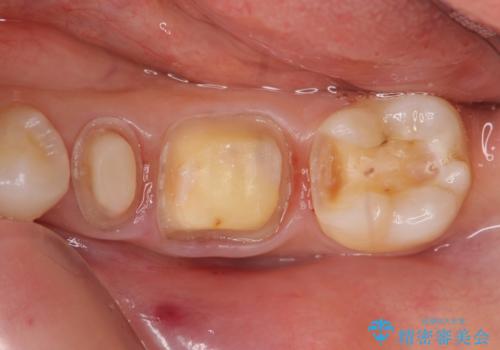

- 左下奥歯の銀歯が気になると来院された方の症例です。

左下7はセラミックインレーによる修復を行い、左下5、6はオールセラミッククラウンによる補綴を行いました。

- オールセラミッククラウン…¥100,000×2、仮歯…¥10,000×2、ファイバーコア…¥20,000、セラミックインレー…¥70,000費用は治療当時の料金となります